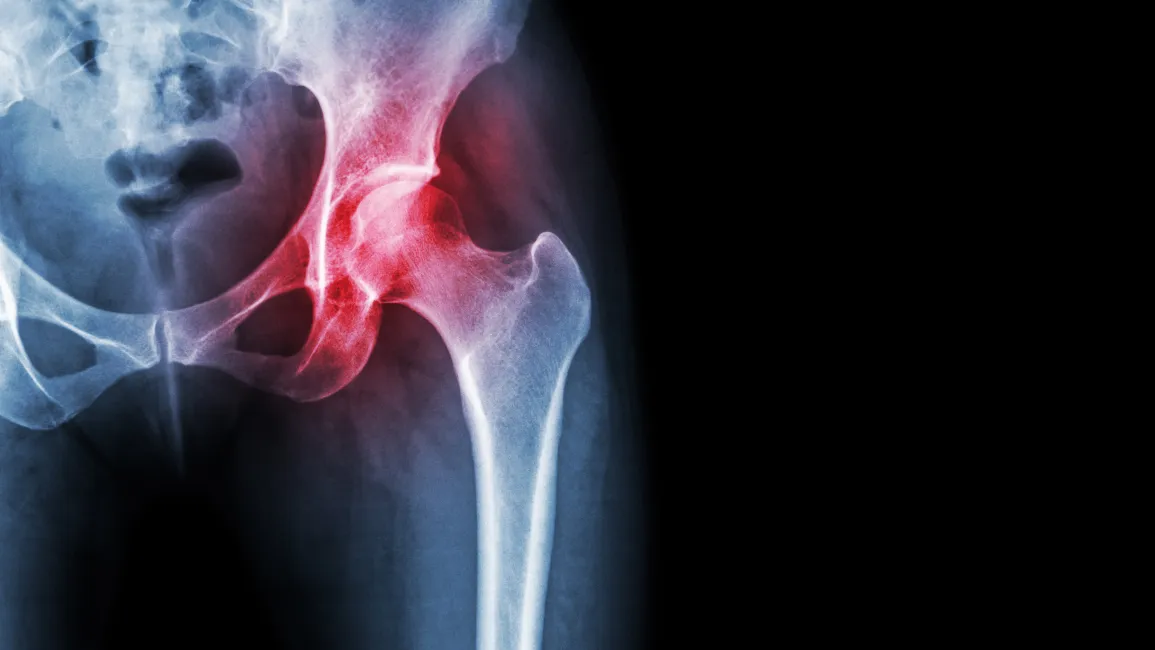

The progression of degeneration in the hip joint is the cause of most chronic hip pain. Although the symptoms may be very insidious at first, the process of degeneration typically takes many years to develop. If not addressed, this degeneration results in bone-on-bone deterioration and the eventual total joint replacement of the hip. In many cases, symptoms do not become severe until near the end stages. This typically means that many arthritis hip pain patients do not seek treatment or get x-rays until it is too late.

Symptoms of hip joint degeneration often vary depending on the severity of the case and where the damage to the joint has taken place. Some patients will experience pain with every activity they do, while others may only experience pain with extremely specific activities.

The best hip pain surgeons in Roanoke, Virginia encourage their patients to explore all conservative paths before getting total hip replacement surgery. Most traditional medical treatments for hip pain symptoms focus on reducing inflammation in and around the joint, which usually involves medication, steroid injections, and/or physical rehabilitation. This approach works best for less severe conditions, such as bursitis. One consideration with steroid injections is that the purpose is not to address the underlying cause of pain, but rather, to focus on simply reducing inflammation. Oftentimes this will provide noticeably short-term relief of symptoms at the expense of the joint and hasten the degenerative process.